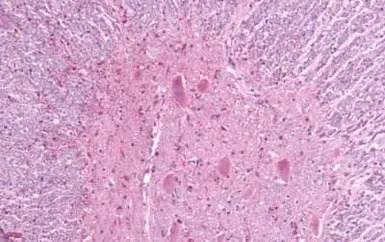

IHC-P analysis of human brain, glioblastoma tissue using GTX71787 MRGPRF antibody.

Antigen retrieval : Heat-induced antigen retrieval